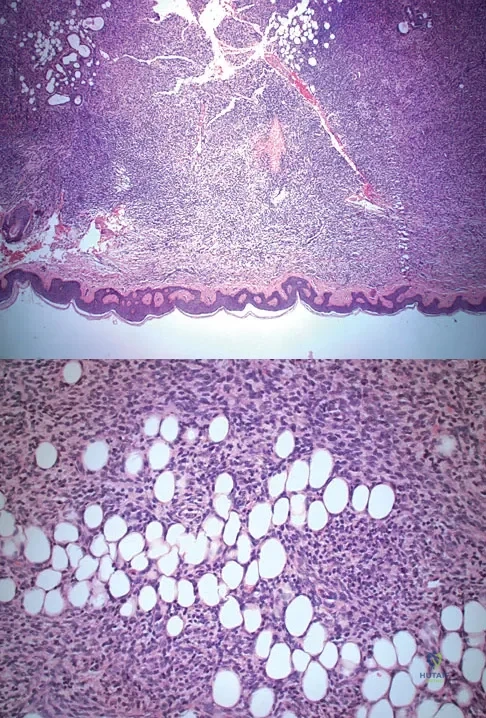

The biopsy specimens seen in Figures 55a and 55b are from a lytic lesion in the sacrum of a 58-year-old man. What is the most likely diagnosis?

Explanation